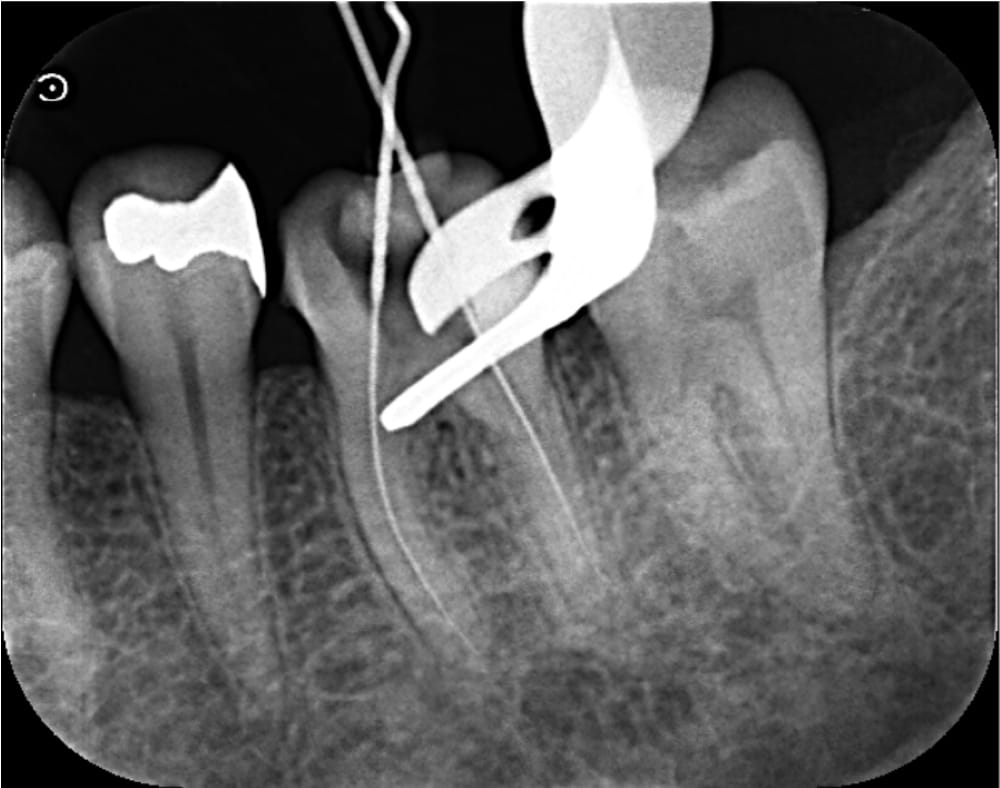

精密根管治療 1回目